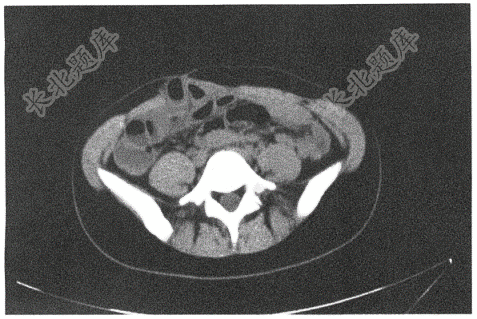

- 单项选择题女性,25岁,肠吻合术后22年,腹痛发热3天就诊。查体:腹平软,右腹部见手术疤痕,右下腹轻压痛,无反跳痛,肠鸣音无亢进。腹部CT所示如图。考虑诊断( )

A、腹壁切口疝

B、腹壁疝

C、腹壁肿块

D、腹壁脓

E、以上均不对